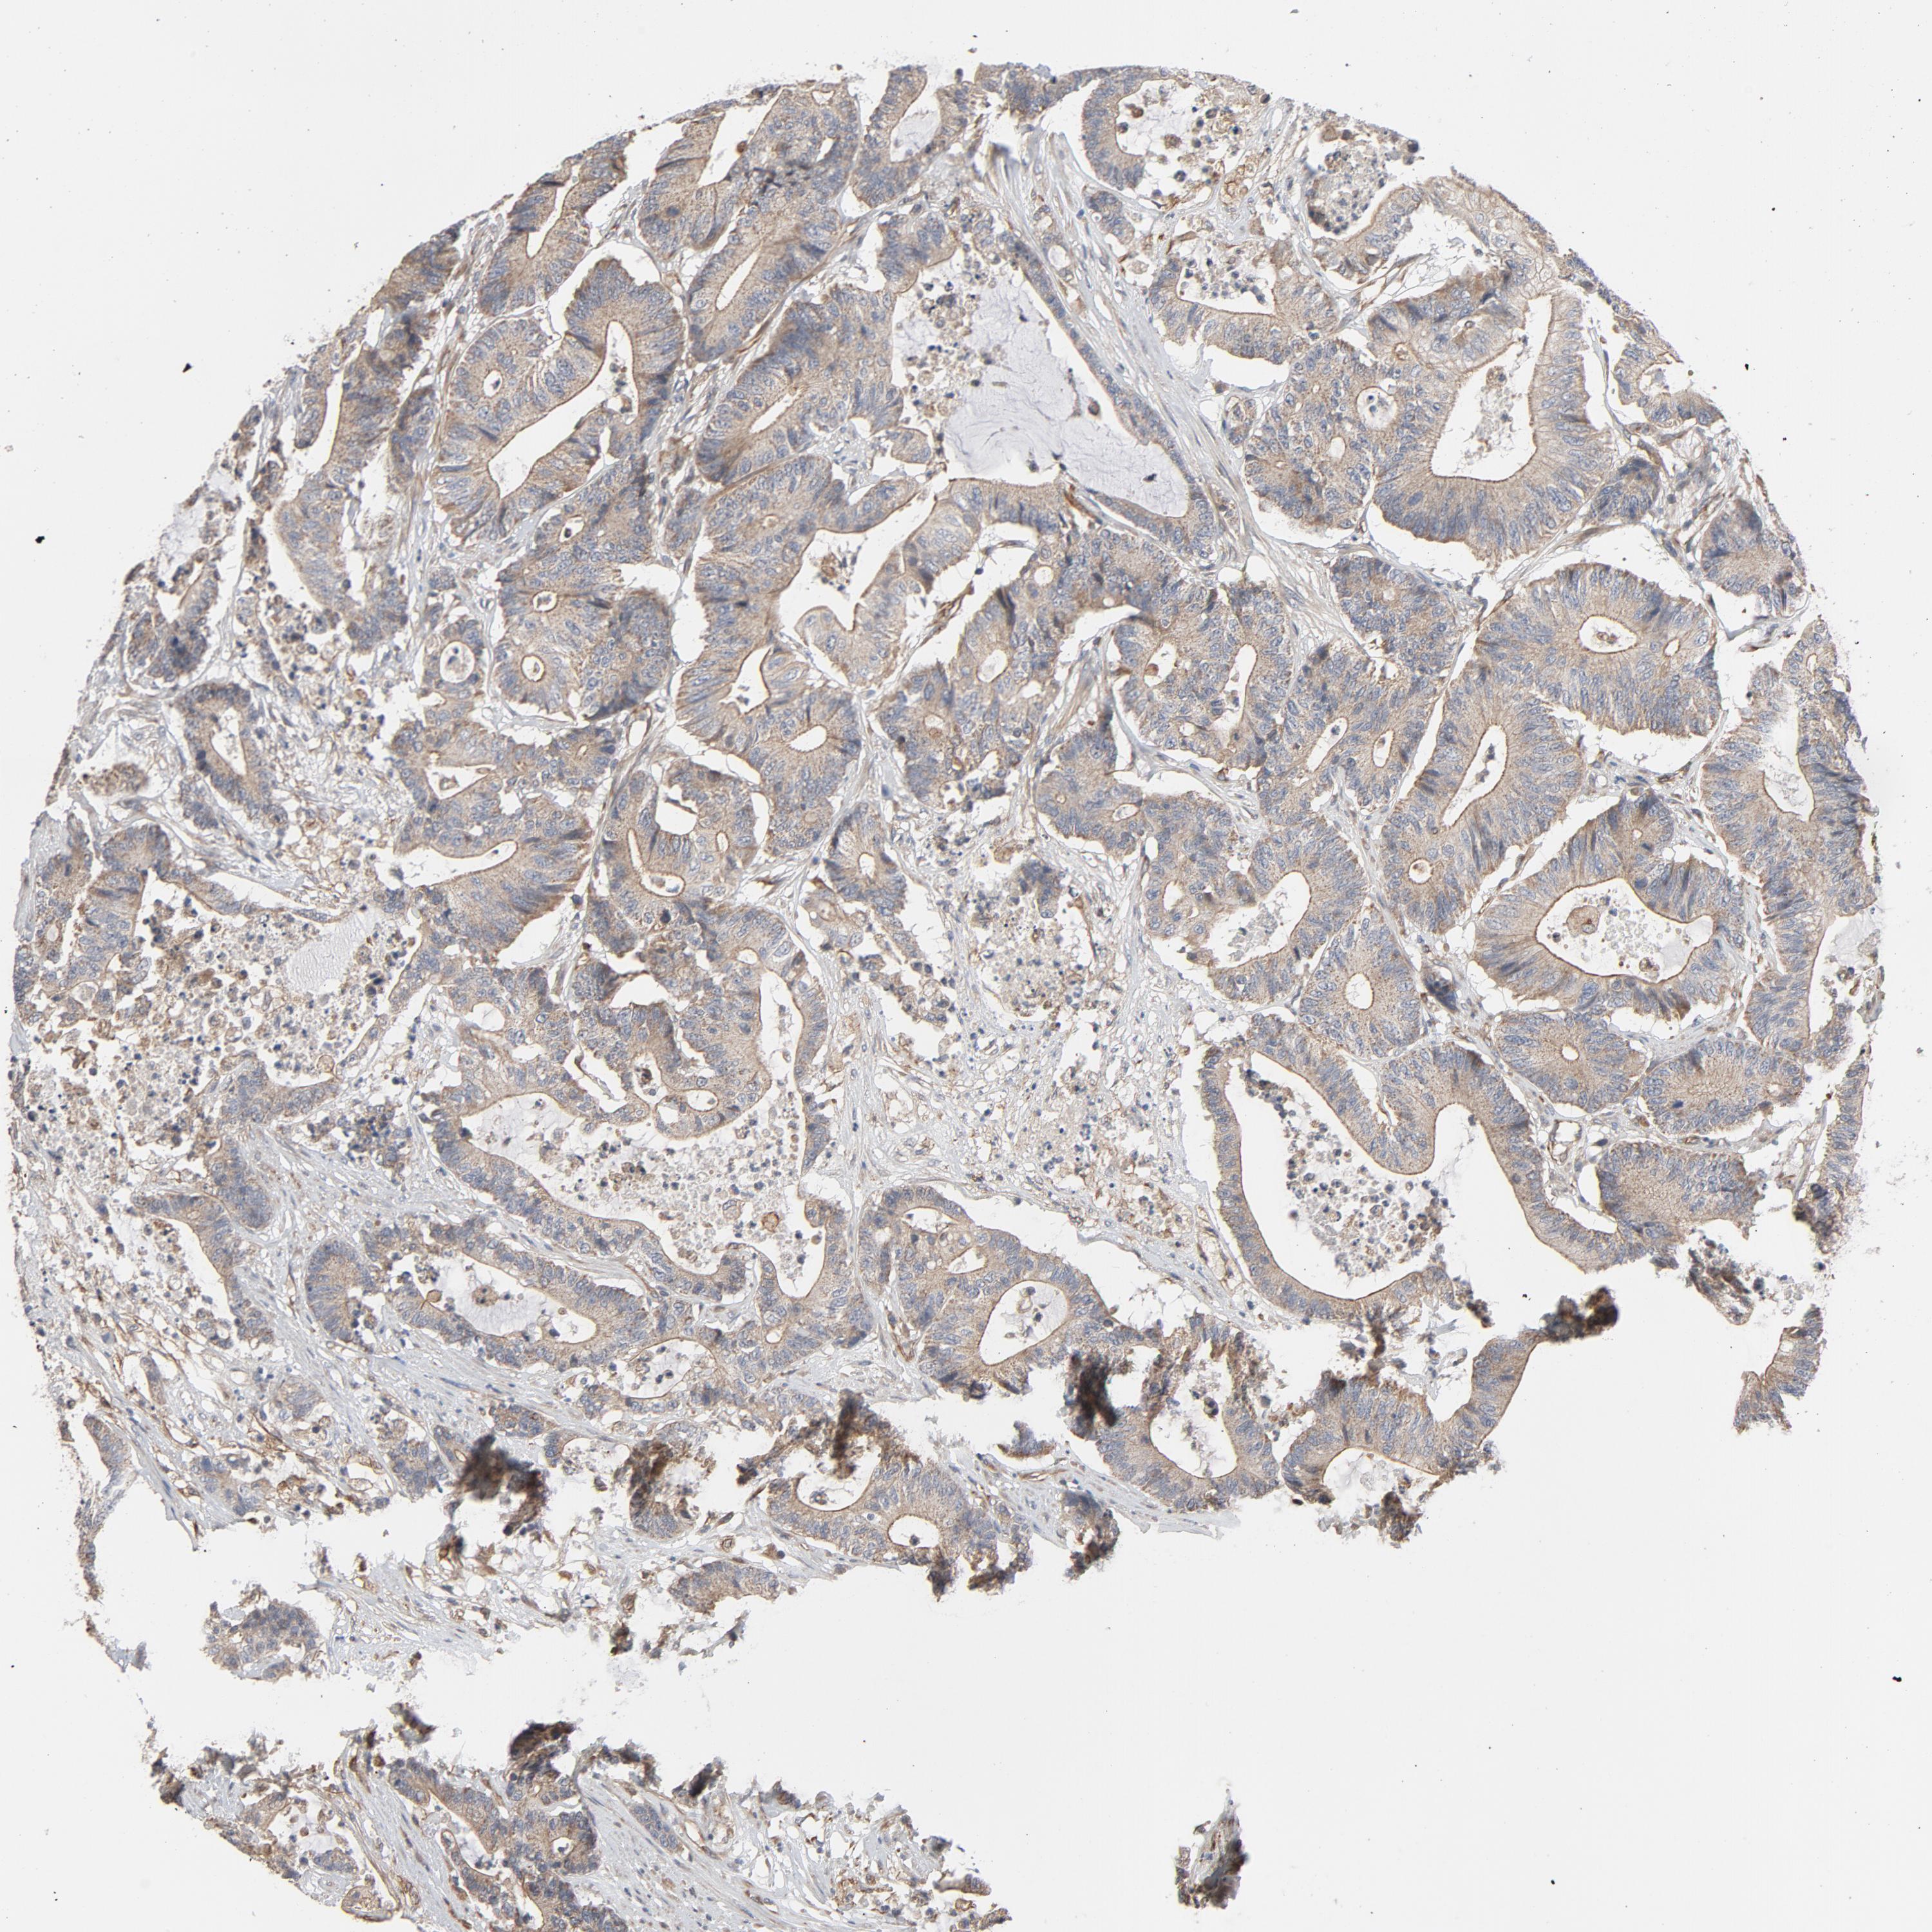

CANCER COLORECTAL CANCER Show tissue menu

Colorectal cancer

Colon adenocarcinoma